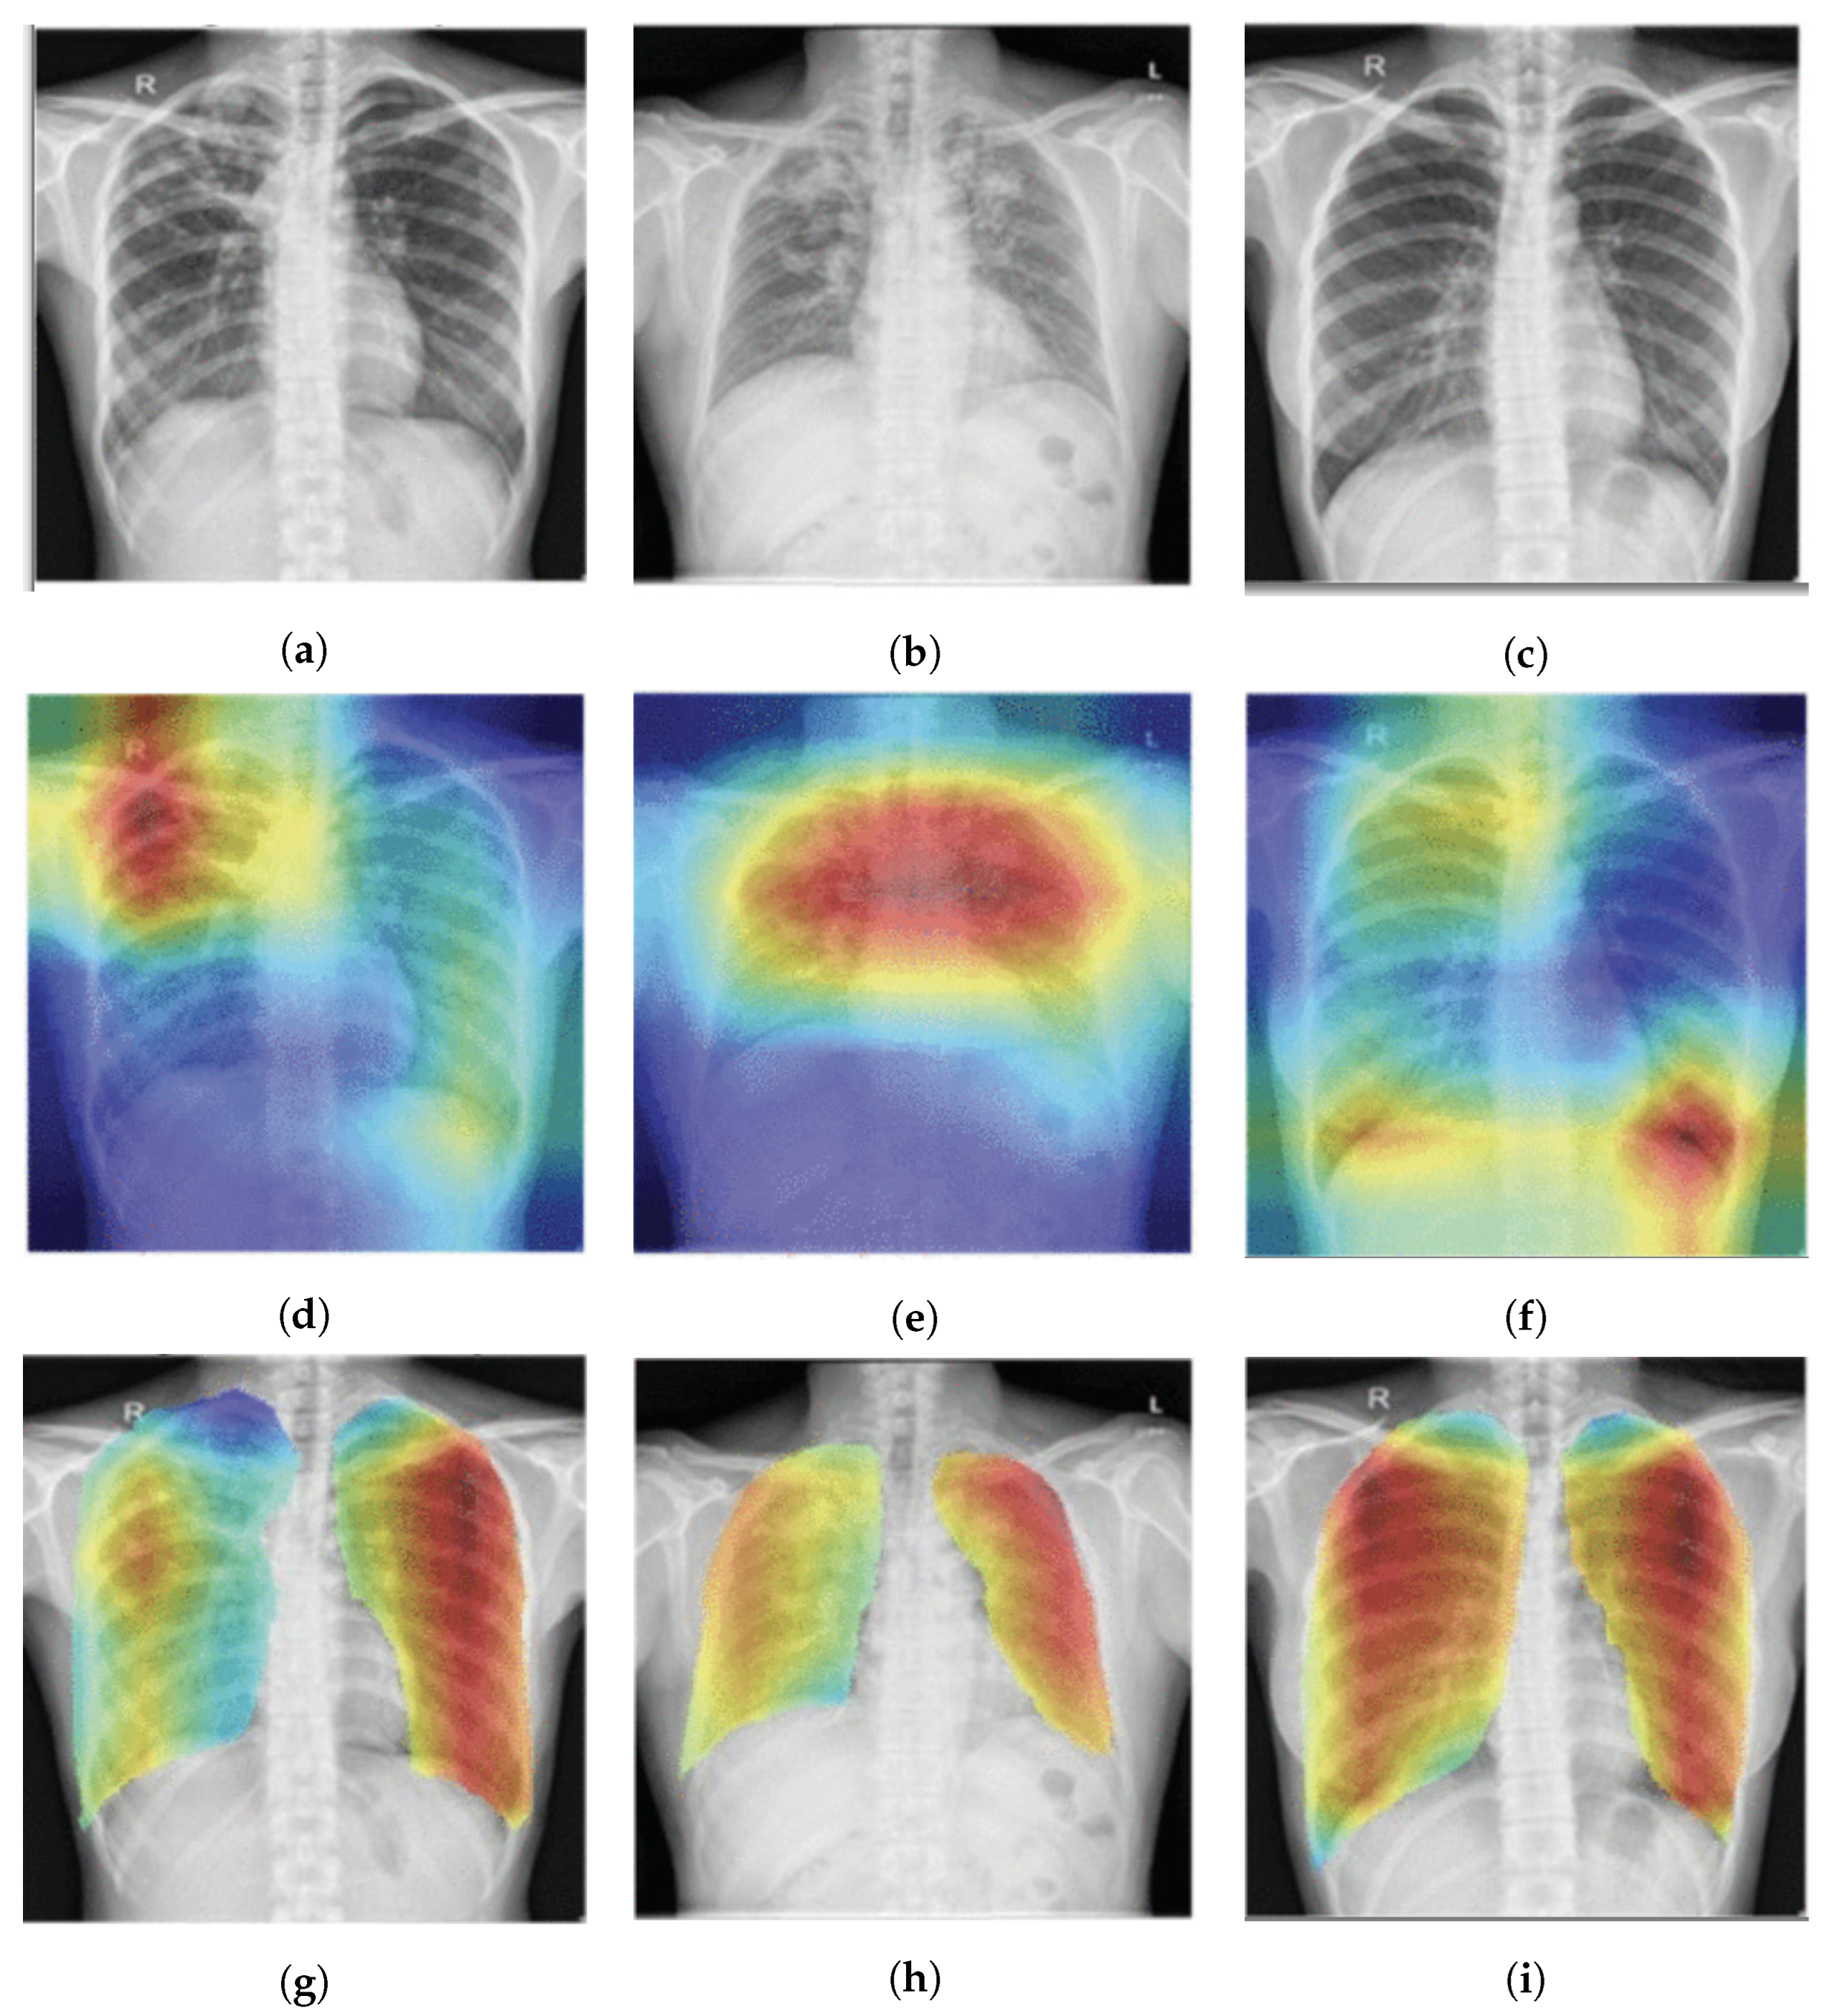

| Wang et al., 2018 [104] | ChestX-ray14, Indiana | Multilevel attentions and saliency-weighted global average pooling |

| Ouyang et al., 2020 [107] | NIH ChestX-ray14 and CheXpert datasets | Hierarchical attention network [80] |

- Wang, X.; Peng, Y.; Lu, L.; Lu, Z.; Summers, R.M. Tienet: Text-image embedding network for common thorax disease classification and reporting in chest X-rays. In Proceedings of the IEEE Conference on Computer Vision and Pattern Recognition, Salt Lake City, UT, USA, 18–23 June 2018; pp. 9049–9058. [Google Scholar]

- Ouyang, X.; Karanam, S.; Wu, Z.; Chen, T.; Huo, J.; Zhou, X.S.; Wang, Q.; Cheng, J.Z. Learning hierarchical attention for weakly-supervised chest X-ray abnormality localization and diagnosis. IEEE Trans. Med. Imaging 2020, 40, 2698–2710. [Google Scholar] [CrossRef]